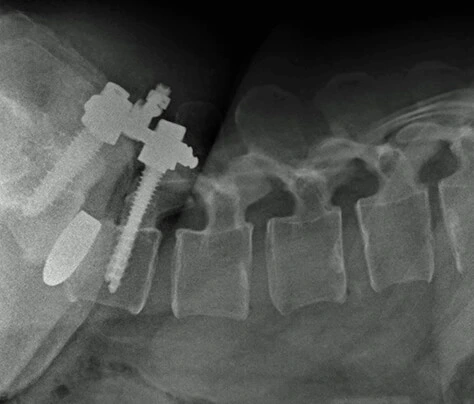

Fracturas de la columna vertebral:

Son heridas en la columna vertebral en las que la espina se comprime anormalmente. Suelen presentarse después de traumas o accidentes severos como caídas o choques en auto, cuando toda la fuerza recae verticalmente en la columna vertebral y se rompe una o más vértebras.

El riesgo de sufrir una lesión de este tipo, es que es posible que aparezcan graves daños en las estructuras nerviosas en incluso puede producirse la parálisis en los brazos y las piernas.